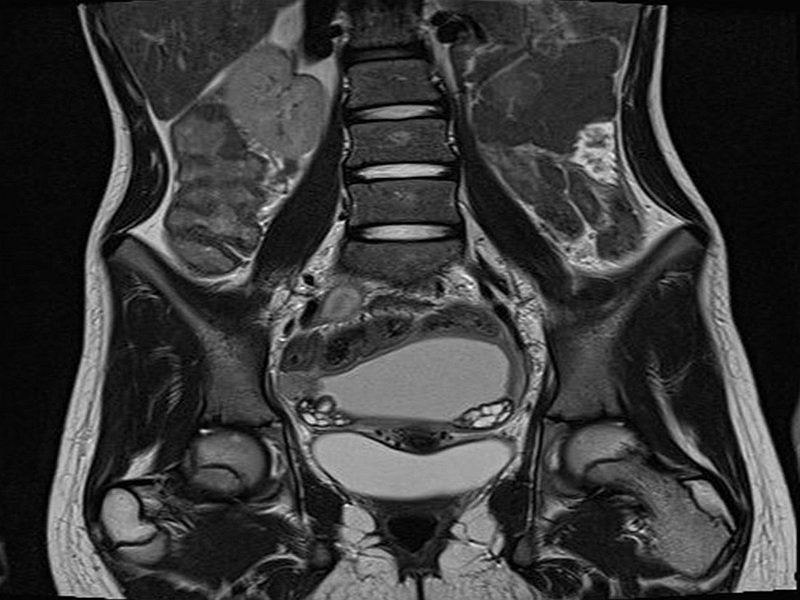

При сканировании органов малого таза у пациентки визуализируются следующие органы: влагалище, тело матки, яичники, придатки (маточные трубы), мочевой пузырь, нижняя часть мочеточников, прямая кишка, лимфоузлы. В ходе обследования врач особое внимание уделит размерам и структуре матки, однородности миометрия, качеству эндометрия, виду и форме шейки матки и влагалища, ширине цервикального канала, особенностям анатомии правого и левого яичников, строению мочевого пузыря, тканевым особенностям прямой кишки и жировой клетчатки. Обзорно будут оценены кости таза и лимфатические узлы.